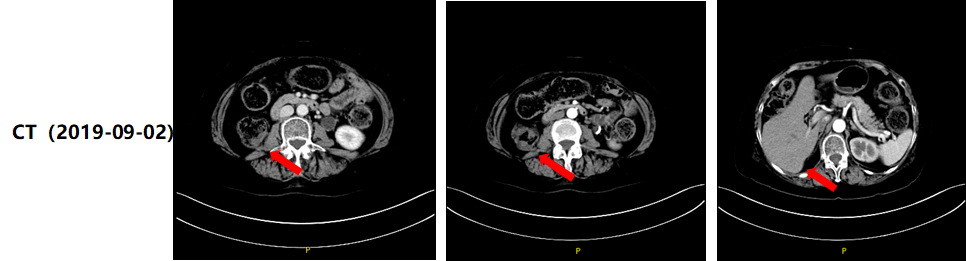

患者术后定期随访,2018年7月31日CT示:肾盂癌根治术+根治性全膀胱切除术后,术区较前相仿(图2)。2019年4月23日CT示:右肾未见,术区右侧腰大肌旁见不规则形软组织样密度影,大小约19.0x16.7mm,可见强化,与周围组织分界欠清;右侧肝脏受侵(图2)。

image002.png

图2.患者术后定期随访CT影像资料